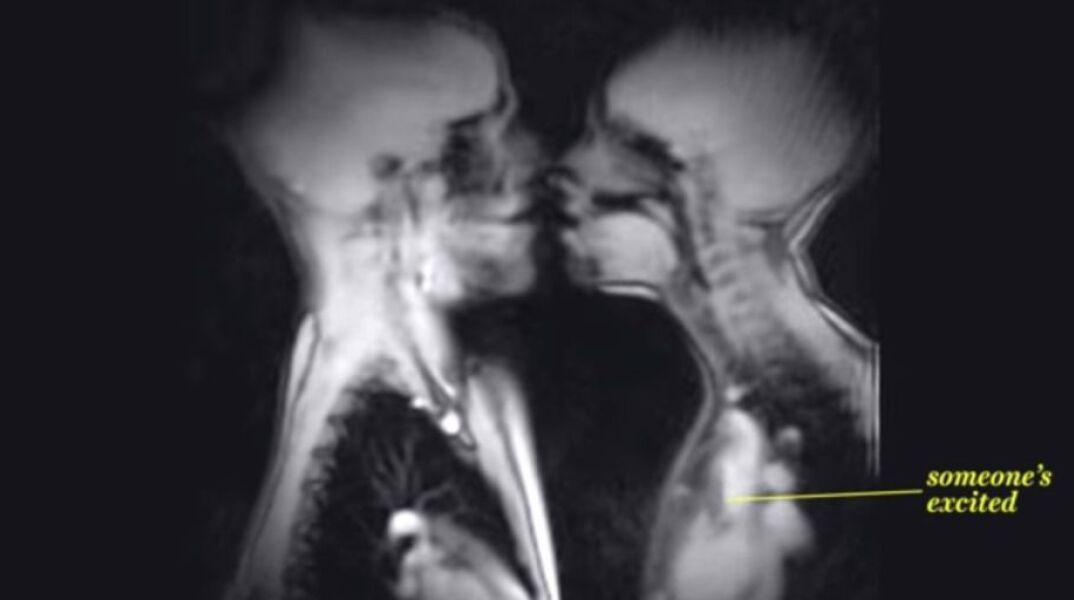

Έτσι είναι το σεξ μέσα από το βλέμμα ενός μαγνητικού τομογράφου

Μοναδικό βίντεο καταγράφει τις πιο μύχιες στιγμές μας

Το μοναδικό αυτό βίντεο δείχνει τι συμβαίνει στο εσωτερικό του ανθρώπινου σώματος κατά τη διάρκεια της σεξουαλικής πράξης. Το απόσπασμα αποκαλύπτει λεπτομερειακά τα διάφορα στάδια της συνουσίας, ξεκινώντας από την αύξηση του καρδιακού ρυθμού όταν δύο άνθρωποι φιλιούνται.

Το εντυπωσιακό μοντάζ συμπεριλαμβάνει επίσης μια γέννηση, ένα πρόσωπο να πίνει χυμό, κάποιο άλλο να φυσά τρομπέτα, καθώς και ένα ζευγάρι πνευμόνια που αναπνέουν.

Στον μαγνητικό τομογράφο δημιουργούνται κινούμενες εικόνες με τη βοήθεια μαγνητικών πεδίων που αλληλεπιδρούν με τα πρωτόνια μέσα στο ανθρώπινο σώμα.